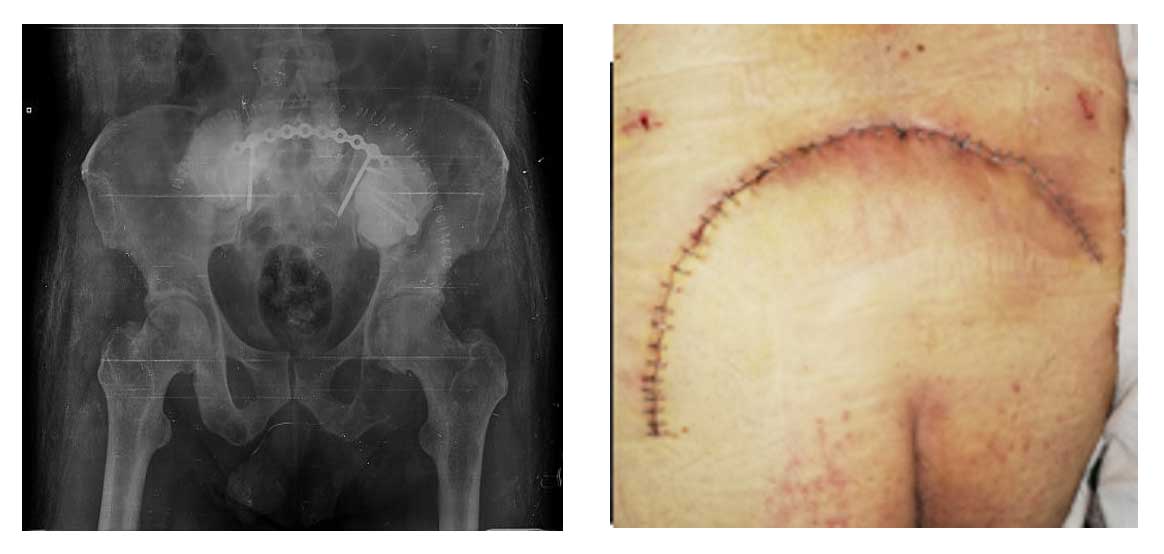

Ameliyat Esnası: Tümörün temizlendikten sonra oluşan boşluğun kemik çimentosu ile doldurulması ve titanyum plak ile güçlendirilmesi görülmekte.

Ameliyat Sonrası: Tümörün temizlendikten sonra oluşan boşluğun kemik çimentosu ile doldurulması ve titanyum plak ile güçlendirilmesi ve yara iyileşmesi görülmekte.